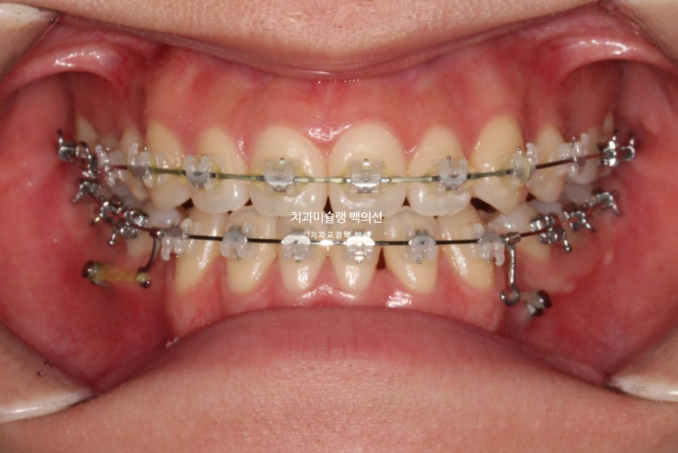

클리피씨 선택하셨고 당일 치료 들어갔습니다.

24.09

위 앞니는 최대한 뒤로 들어가지 않도록 유지하면서, 아래 앞니는 최대한 뒤로 많이 넣기 위해 아래에 교정용 나사를 2개 심었습니다.